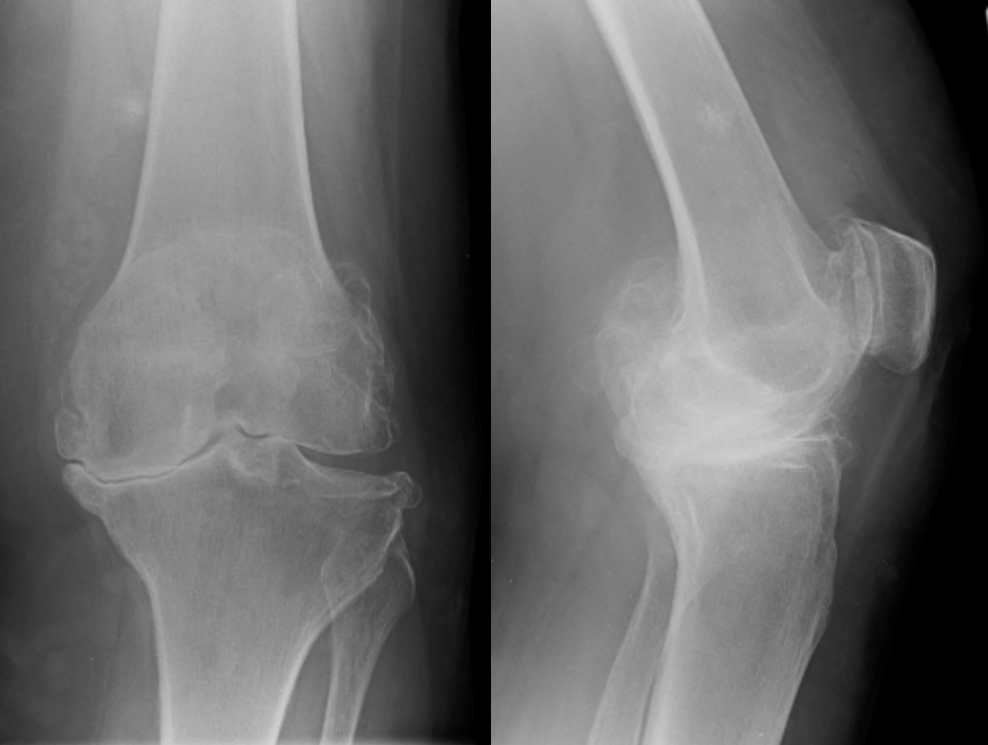

The worn cartilage in arthritis can usually be assessed with an x-ray. Although the cartilage is not visible, if the x-ray is performed with the patient standing, the bones will appear to touch in areas where the cartilage is very worn because there is no longer any cartilage separating them.